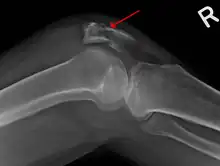

Fracture de rotule

La radiographie déterminera s'il y a oui ou non bel et bien une fracture de la rotule. Si oui, le chirurgien orthopédiste pourra décider d'opérer.